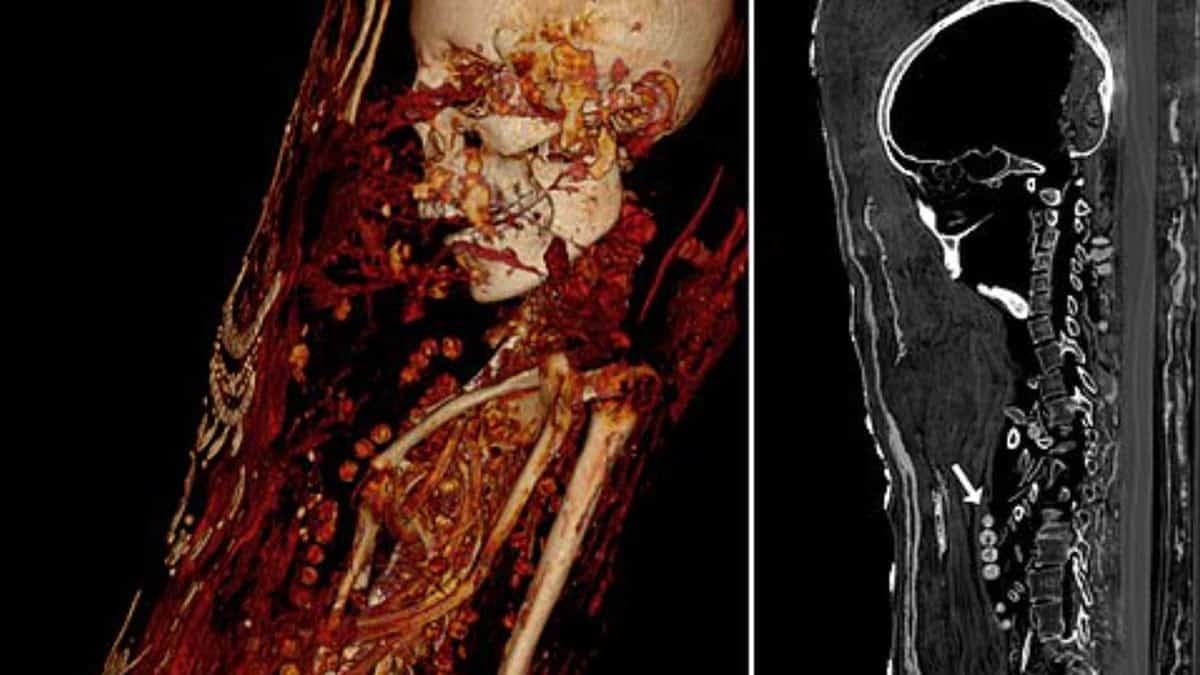

Bilimadamlarının bilgisayarlı tomografi ile incelediği mumyaların tüm organlarıyla birlikte mücevher ve altın sikkelerle gömüldükleri ortaya çıktı.

Araştırmacılar, incelemelere göre, söz konusu üç kişinin de sağlık problemleri nedeniyle erken yaşta öldüklerini belirtti.